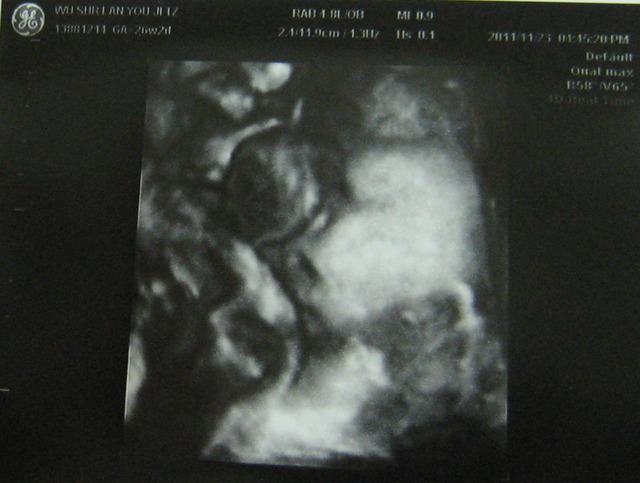

有,次也做4D,然我看到的是模糊的影像,但有次看到瓦力正在打哈欠?的子,我得好好玩,也很多人有看胎在肚子打哈欠(嘴巴)的子,所以跟大家分享。往下看就找到喔。